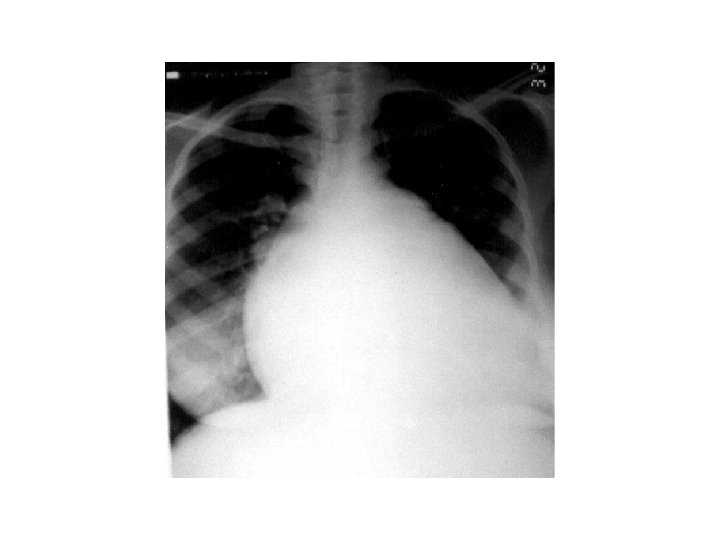

INVESTIGATION § CBC § U+E § LFT § Cardiac enzymes § CXR § ECG § Echocardiogram